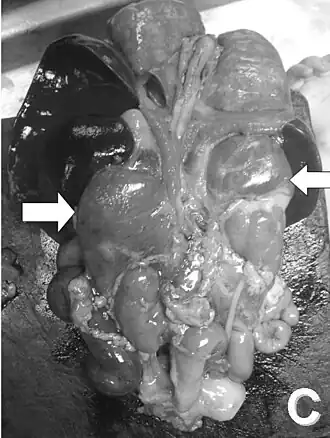

Вскрытие новорождённого. Стрелками указаны увеличенные надпочечники | |